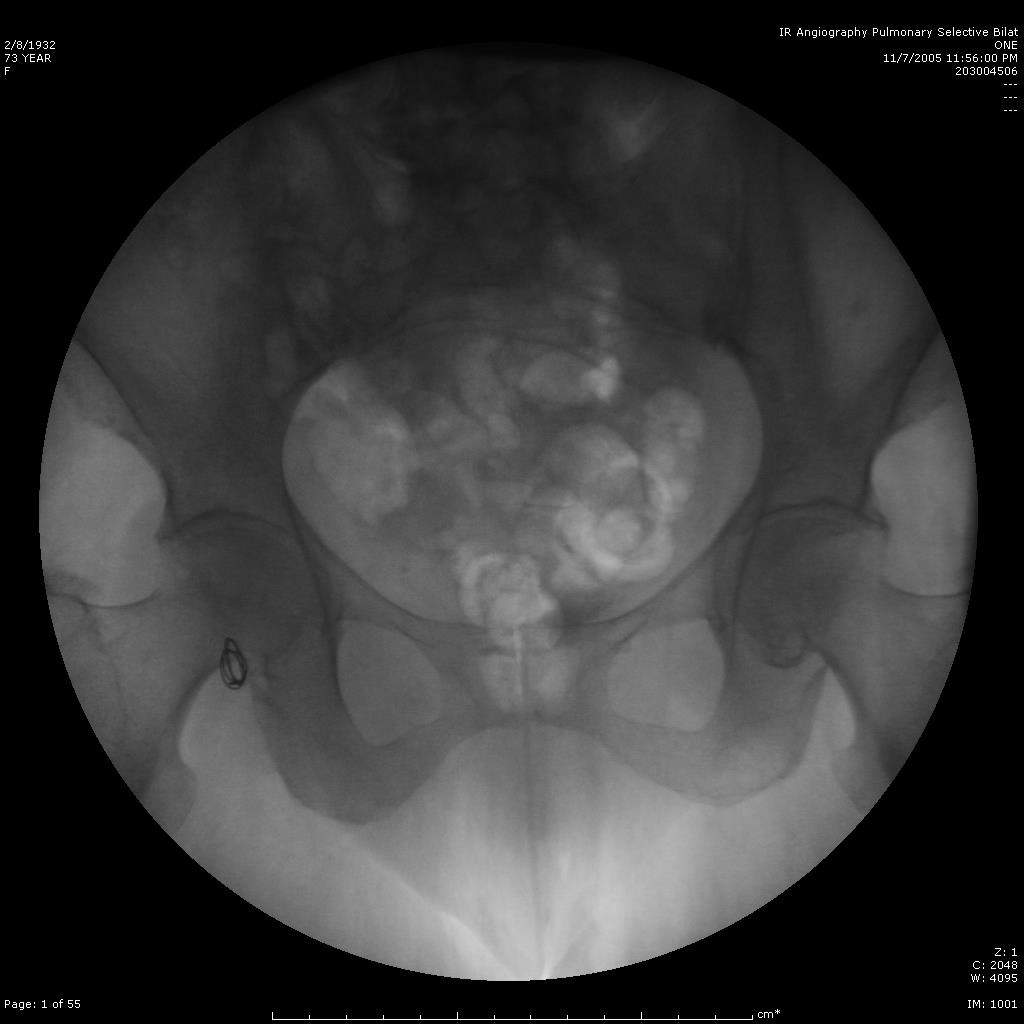

肺动静脉畸形

肺动静脉畸形分为单发、多发和弥漫性 |

这一例为多发性肺动静脉畸形 |